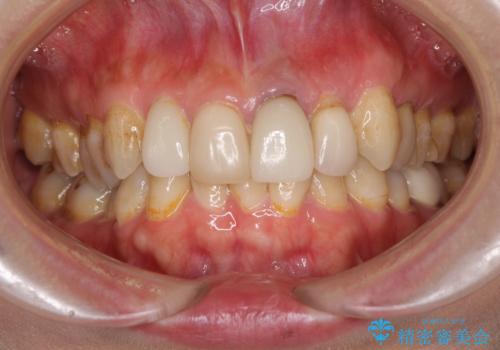

歯肉移植を用いた前歯のオールセラミックブリッジ

- 前歯が折れてしまい、ブリッジによる補綴治療を希望して来院された患者様です。

折れている前歯は抜歯をし、痩せてしまう歯肉は移植術により増大させることで審美面を回復した後、オールセラミックブリッジにて補綴することとしました。

インプラントかブリッジか悩むところでしたが、既に治療されている前歯のクラウン周りの変色が気になっていたため、ブリッジにより色調を合わせたオールセラミックを装着することを選択しました。

歯肉ラインや歯の形態、色調を整えることができ、患者様には大変満足していただきました。